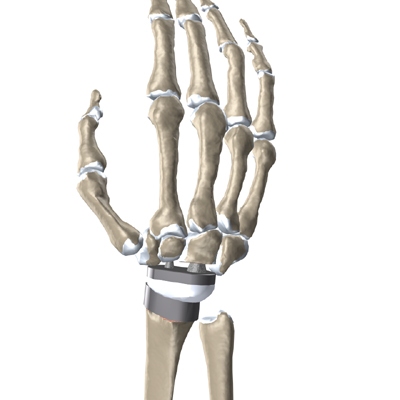

Modern artificial wrist joints are made of metal and plastic. The part that fits against the end of the radius bone of the forearm is called the radial component. It is made up of two pieces. A flat metal piece is placed on the front part of the radius. It has a stem that attaches down into the canal of the bone. A plastic cup fits onto the metal piece, forming a socket for the artificial wrist joint.

The part that replaces the small wrist bones is called the distal component. This piece is made completely of metal. It is globe shaped to fit into the plastic socket on the end of the radius. The metal distal component is attached by two metal stems that fit into the hollow bone marrow cavities of the carpal and metacarpal bones of the hand.

The plastic used in artificial joints is tough and slick. It allows the two pieces of the new joint to glide easily against each other as you move your wrist. The ball and socket allow movement of the wrist in all directions.

The hand bones and the radius bone of the forearm are then prepared with special rasps. The rasps are used to:

Bore Holes

in the bone for the metal stems of the:

Replacement Joint

The surgeon will take some time to get the stems to fit tightly. The joint is put in place and tested through its range of motion to make sure it moves correctly. Once the surgeon is satisfied with the fit, the stems of each metal implant are:

Cemented into Place